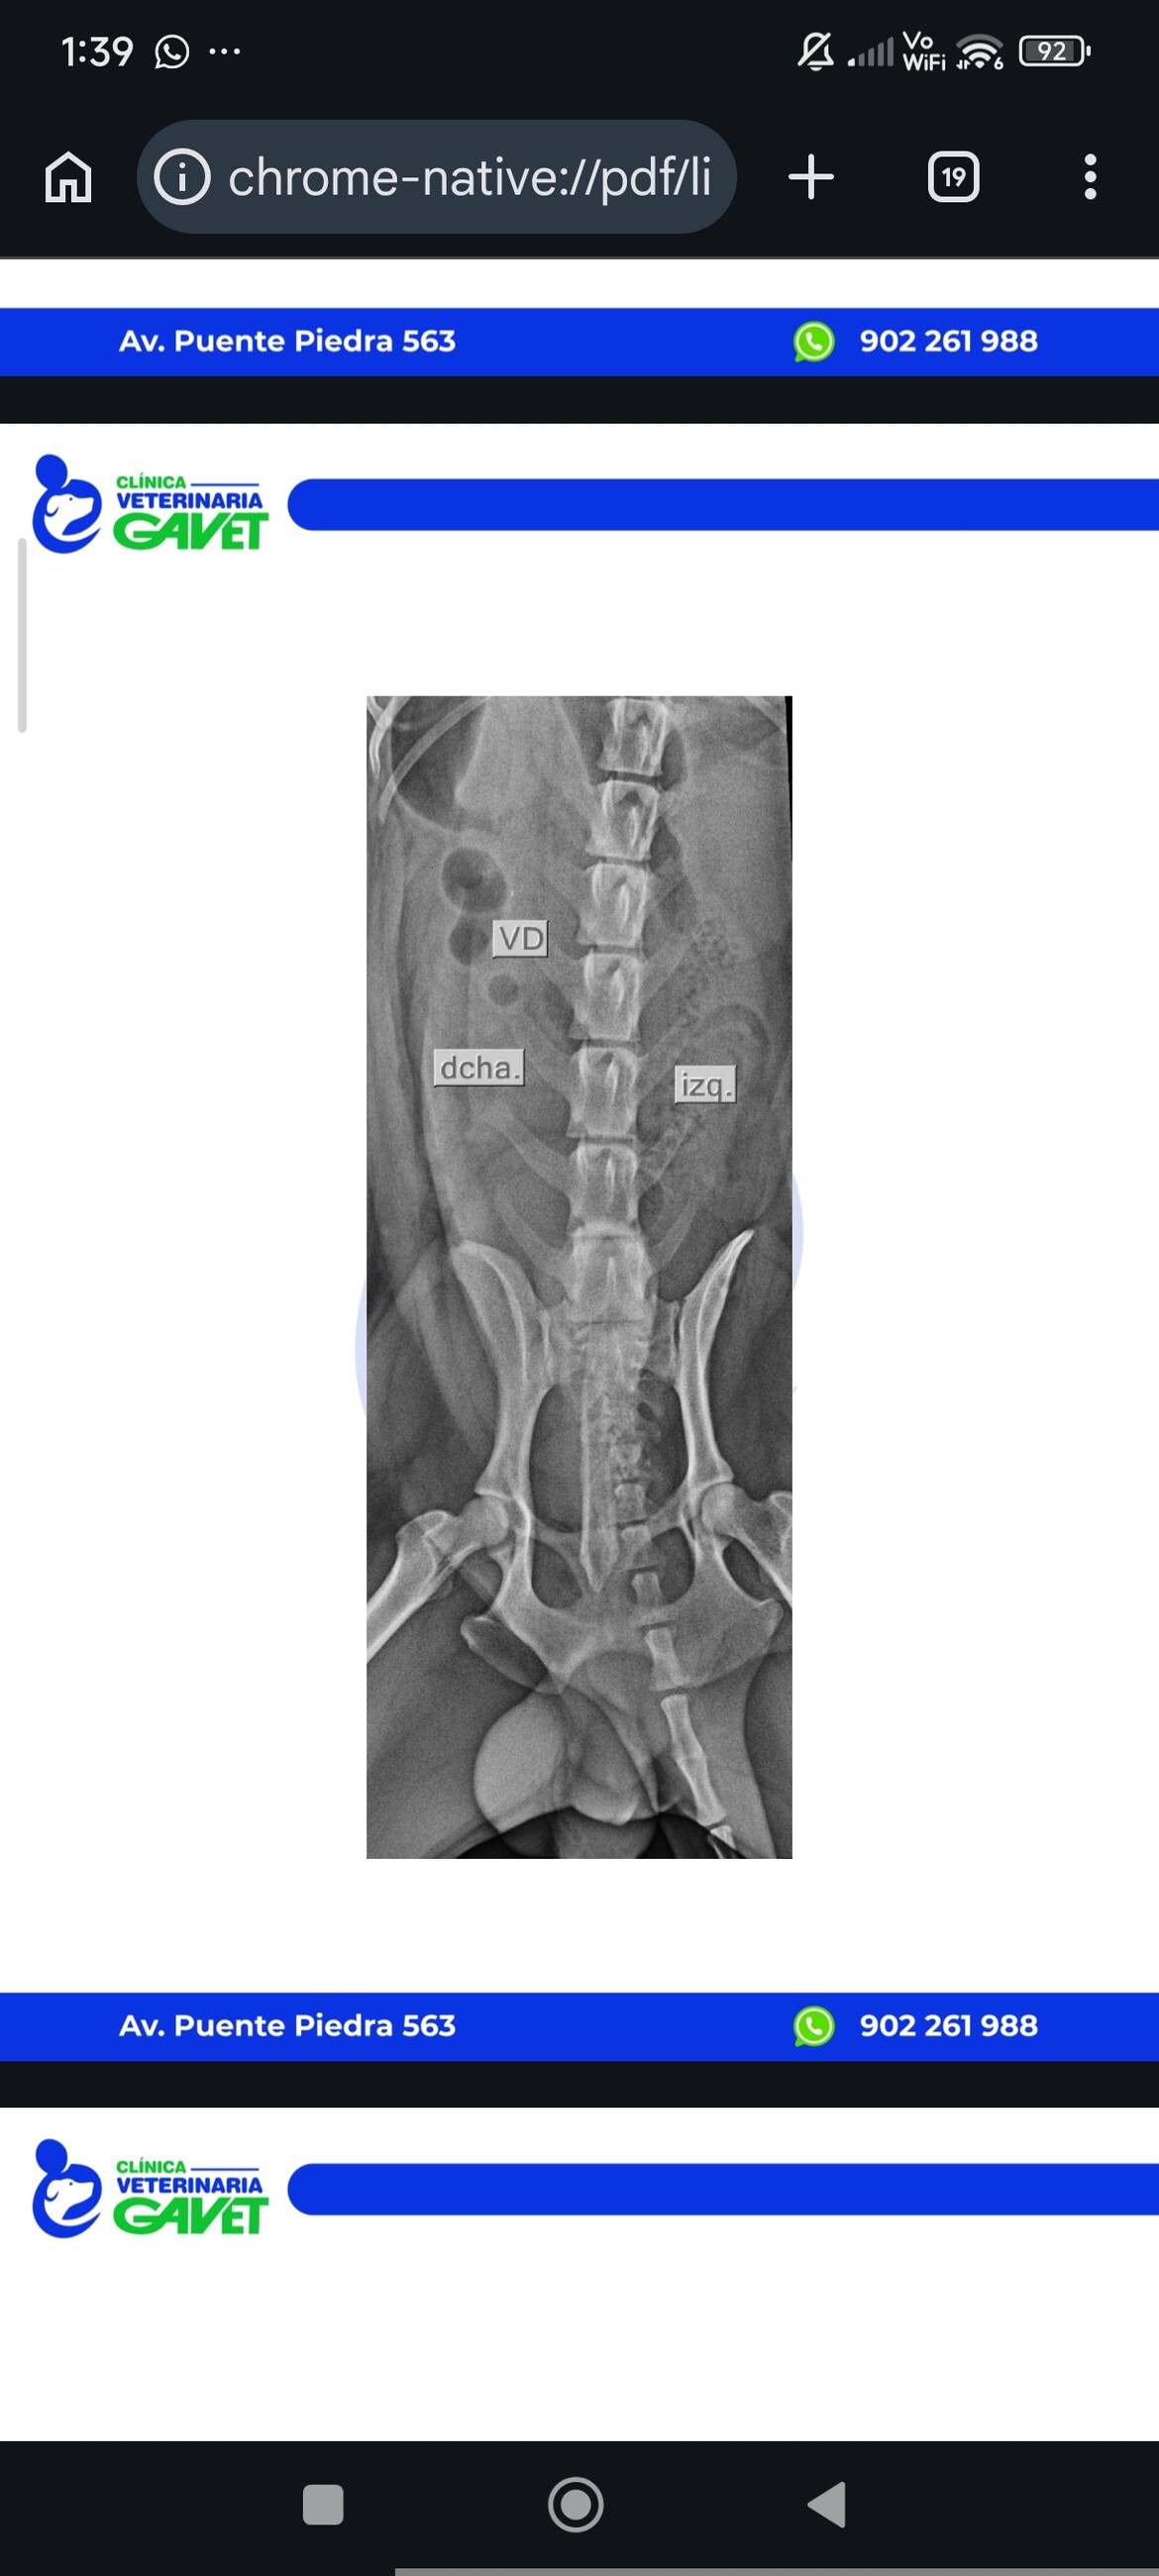

04/04/2026 Balu had an accident and has problems with walking 🥺

He is receiving a treatment for now for Inflammation - he doesn't have any bones broken. But still has problems with walking properly

he had today 06/06/2026 his appointment with a specialist neurologist.

Yesterday he couldn't walk/stand on both rear legs.

Today he can use his rear left leg.

Right rear leg while he is trying to walk/stand stays "straight", after he sit down or rest his leg is relaxed - doctor says it is a good sign that probably he can regenerat - because neuro signals change - (his leg doesn't stay all the time straight)

We help him urinate by pressing the bladder.

But today during the anti-inflammatory injection he urinated by himself - it is a very good sign, because he can gain back his sensibility to control nerves and strength, and probably get back to be healthy.

He needs to have TL MRI scan (Resonancia Magnética) to be sure if he doesn't need an operation to be able to walk. We hope he will be walking - Doctor says it is possible with quick reaction and rehabilitation plus medicine and we hope no operation well be needed. But ow will be sure after MRI scan